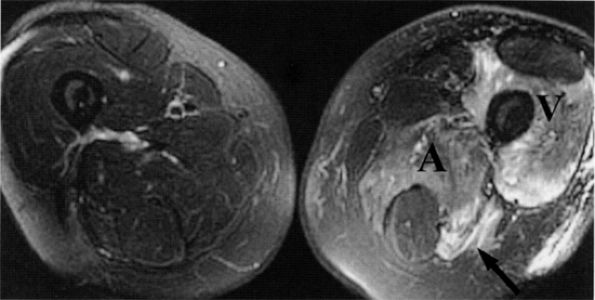

FIGURE 6.14 ● Plexiform neurofibromatosis. (A) Coronal T2-weighted fat-suppressed image depicting fusiform enlargement and increased signal of the right (arrows) and left (arrowheads) sciatic nerves. (B) Axial T2-weighted fat-suppressed image demonstrating the “bag of worms” appearance of the right sciatic nerve (black arrow). Note an intramuscular neurofibroma in the rectus femoris muscle (white arrow).